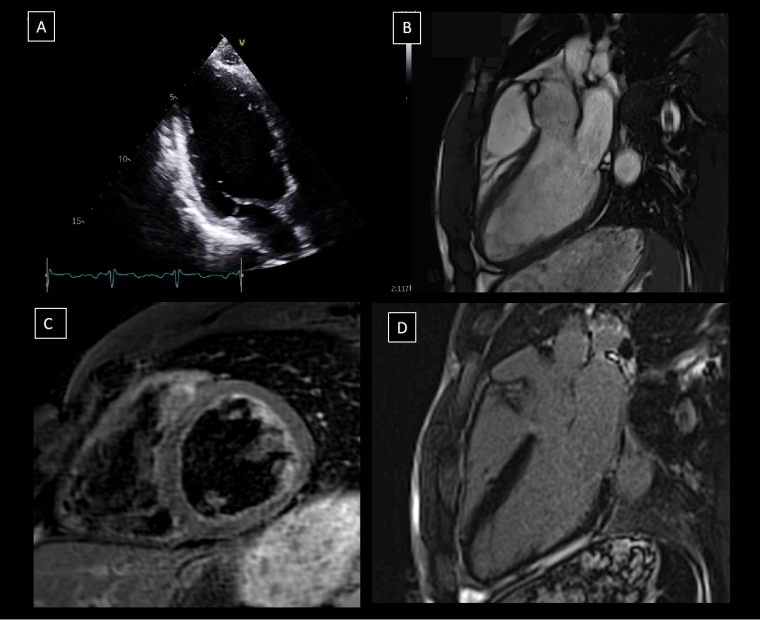

Figure 2. Representative multimodality imaging of a 30-year-old elite endurance athlete who complained of dizziness while exercising. A) The apical 2-chamber TTE view showed inferolateral dyskinesia (Video 2.1). B) 3-chamber view SSFP cine sequences, that confirmed severe inferolateral midventricular and apical hypokinesia (Video 2.2). C) Short-axis STIR sequence that did not show oedema in the inferolateral segment and D) 3-chamber view LGE sequence with a large subepicardial inferolateral enhancement. All these features are consistent with an old scar due to a previous myocarditis.

LGE: late gadolinium enhancement; SSFP: steady state free-precession; STIR: short Tau inversion recovery; TTE: transthoracic echocardiography